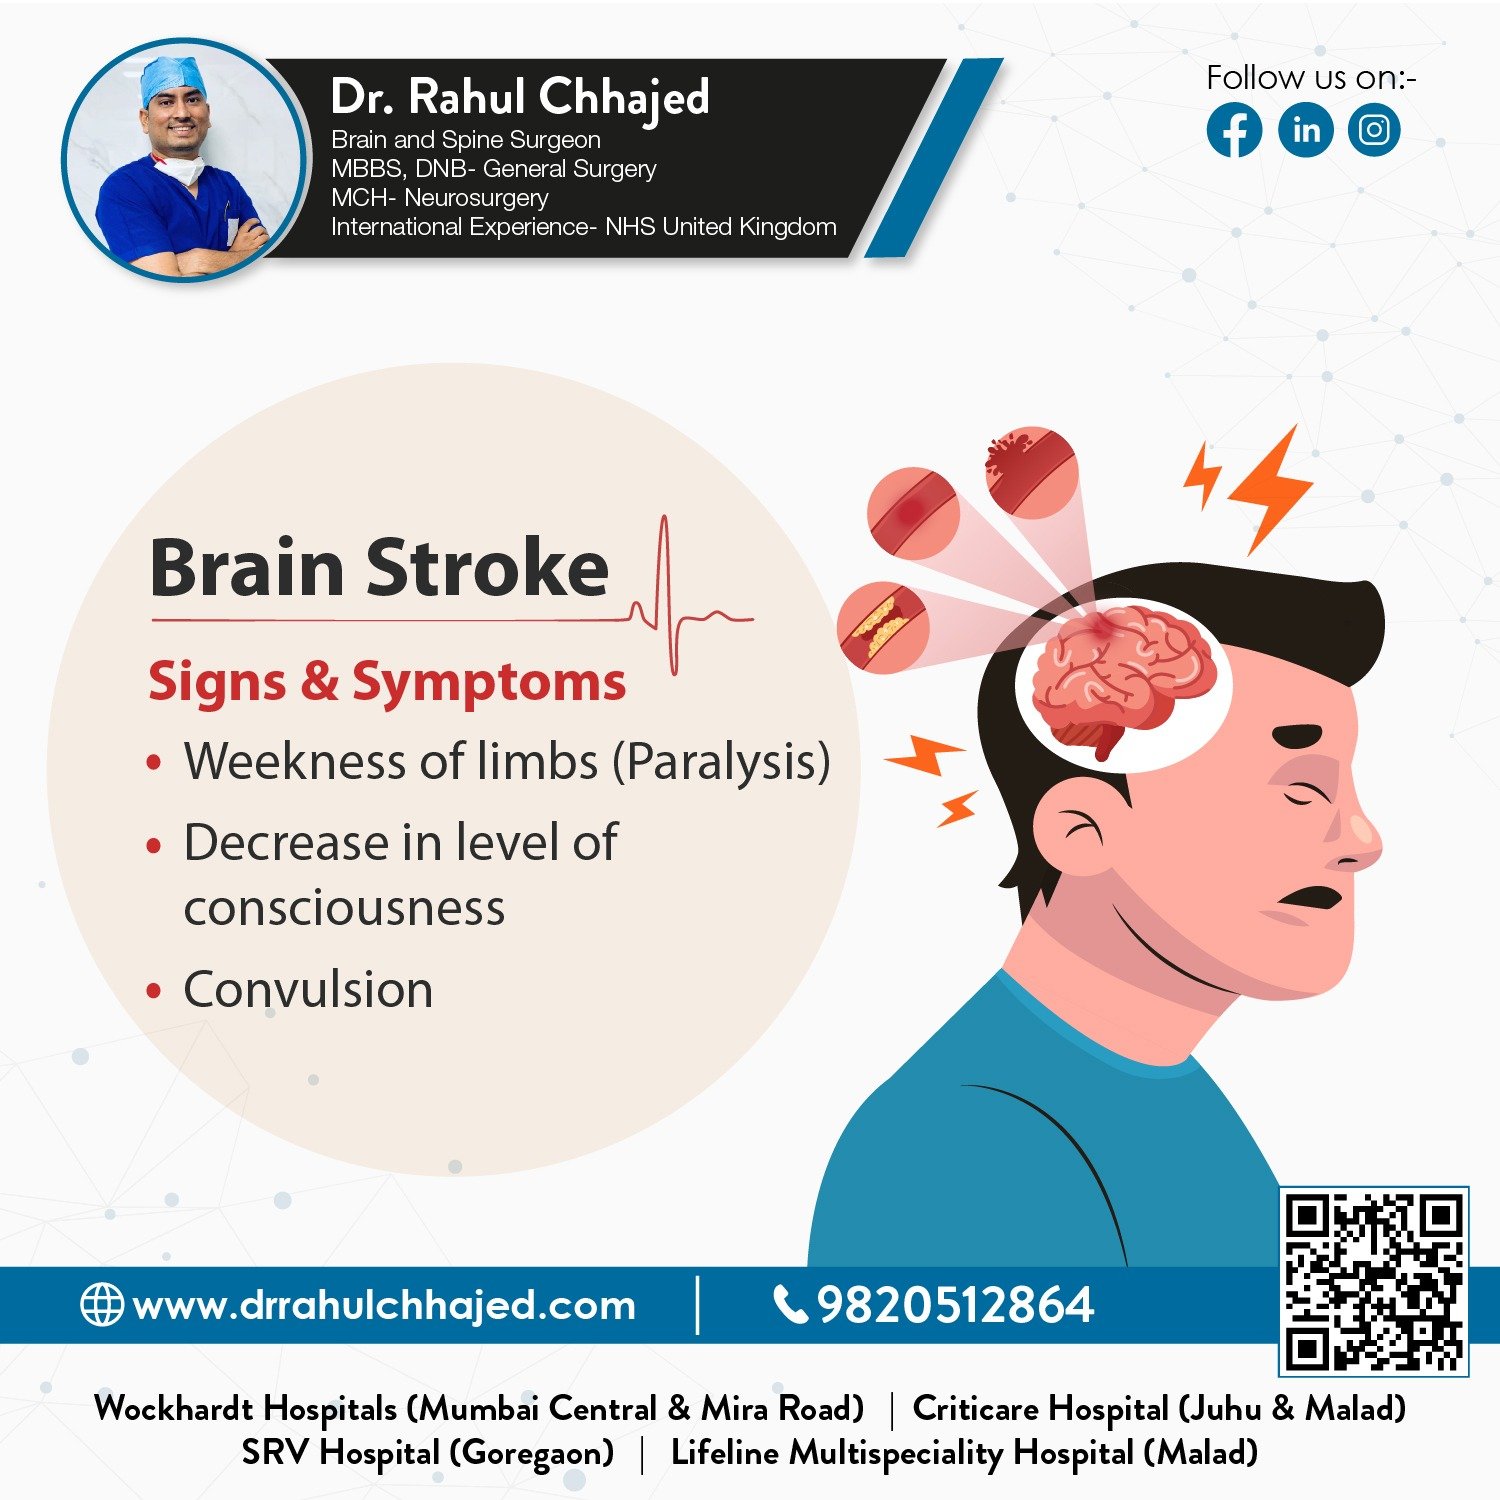

Stroke

A stroke is a medical emergency. We use the latest techniques and technologies to provide the highest quality stroke care, including clot-busting medications, minimally invasive procedures, and advanced rehabilitation programs.

Paralysis

Paralysis can be a life-changing condition that requires specialized medical care. We provide a comprehensive range of treatments for paralysis, including physical therapy, medication, and advanced surgical procedures.

Some of the services provided by Dr. Rahul are Tumor( Cancer), Brain and Spine Trauma, Spine surgery -Minimal Invasive/ open spine surgery, Stroke patients (Paralysis), Back pain-Sciatica, Trigeminal Neuralgia and Neck Pain, Brain haemorrhage, headache-Migraine, etc